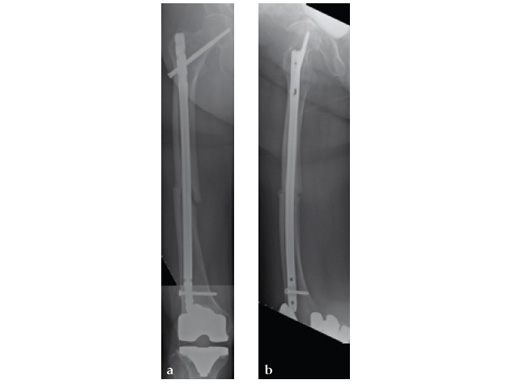

Notice the fracture decrease the emphasis on the anterolateral bow of the femur (See Fig 5a-b).

Note despite the increased in curvature compared to other nails in the market, there is still noticeable malreduction at the fracture site (see Fig 6a-b).